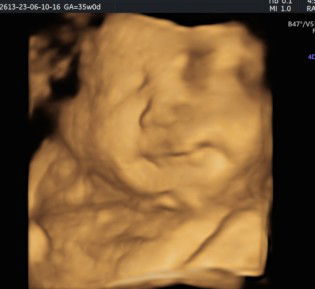

Magbasa paCAS @24weeks po ako. Then after 2weeks na po ako bumalik sa OB ko. Since magkaiba po sa clinic namin yung nagka-CAS and OB talaga. Pero kung iisa lang po mag CAS sayo at OB mo na din sya since ieexplain na din sayo yung result. Pwede naman na siguro yung after a month ka na bumalik. If wala ka pang 7mos. Kasi pag 7mos up dapat 2weeks ng 2week po ang ff check up.

Magbasa pa23 weeks nung nagpa CAS ako nasa 2800 ata yung binayad namin nun . binalik namin sa OB ko yung result nung CAS 26 weeks na kase dinaman inexplain saken nung OB Sonologist yung CAS ko na Open cervix na pala ako that time 26 weeks. Buti naagapan ng OB ko .

Hi po, ako po nung nagpa-CAS, nasa week 22 and 5 days ko po that time, tinaggap na ako pero ang standard daw po talaga dapat is week 23 to 28. kaya advice ko po mga week 26 to 28 kana po magpa-CAS para kitang-kita po yung baby mo.

Hi mommy! Nung binigyan ako ng request ni OB for CAS (26 wks) pinapabalik nya ko after 3wks para dun na lang daw tgnan CAS result ko (hindi po sono si OB) . Hanggang 28 wks lang daw po kasi ang CAS